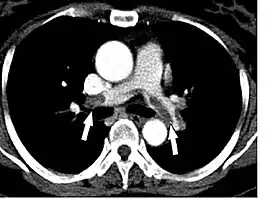

![]() КТ-картина тромбоэмболии главных лёгочных артерий при КТ-ангиопульмонографии. | |

Спиральная компьютерная томография

КТ-ангиопульмонография позволяет обнаружить тромбы в лёгочной артерии. При данном методе датчик вращается вокруг больного, которому предварительно вводится внутривенно контрастный препарат. В результате создаётся объёмная картина лёгких. Однако пациент должен суметь задержать дыхание во время процедуры (несколько секунд). Метод менее инвазивен и более безопасен, чем ангиография[10]. По мнению экспертов Европейского общества кардиологов у больных высокого риска достаточно однодетекторной КТ для подтверждения или исключения ТЭЛА. У больных невысокого риска рекомендуют мультидетекторную КТ, так как она позволяет более чётко выявить тромбы в ветвях лёгочной артерии[18].